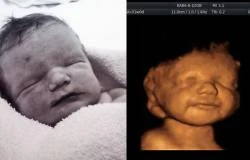

LONDRES, 16 Ene. 13 / 04:01 pm (ACI/EWTN Noticias).- La joven inglesa Katyia Rowe rechazó en varias oportunidades el pedido de aborto por parte de los médicos para su bebé, Lucian Haydes, que iba a nacer con daños cerebrales que le impedirían hablar y caminar y al que le habían diagnosticado una corta vida. Cuando en un ultrasonido (ecografía) 3D lo vio reír y jugar dijo que "yo sabía que no podría terminar con su vida".

Expertos del hospital pediátrico Birmingham confirmaron que el pequeño nunca hablaría ni podría caminar y necesitaría cuidados especiales siempre. Katyia no se amilanó y siguió adelante con el embarazo, haciéndose los ultrasonidos en donde podía ver al niño sonreír, hacer burbujas, patear y mover sus brazos.

"Investigué sobre todos los problemas que tendría para estar preparada en atenderlo, nunca tuve un momento de duda, solo tuve que mirar la ecografía y ver cómo disfruta en el vientre para saber que hacía lo correcto al darle una oportunidad".